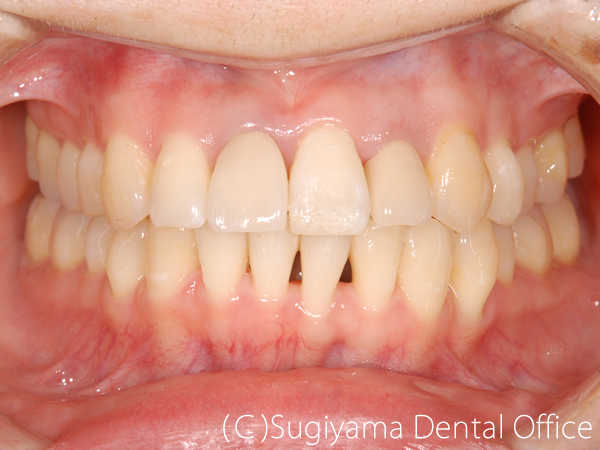

術前症例写真

術後症例写真

下のあごが極端に後ろに引っ込んでいたために、口を閉じた状態だと下くちびるが薄くなり、ほとんど見えない状態だった女性の患者さんです。

かみ合わせの位置を移動させるように矯正治療を行って、正常なかみ合わせを獲得しました。

顔写真はお見せできませんが、上下でバランスが取れたくちびるの厚さになり、とてもきれいな顔立ちになりました。